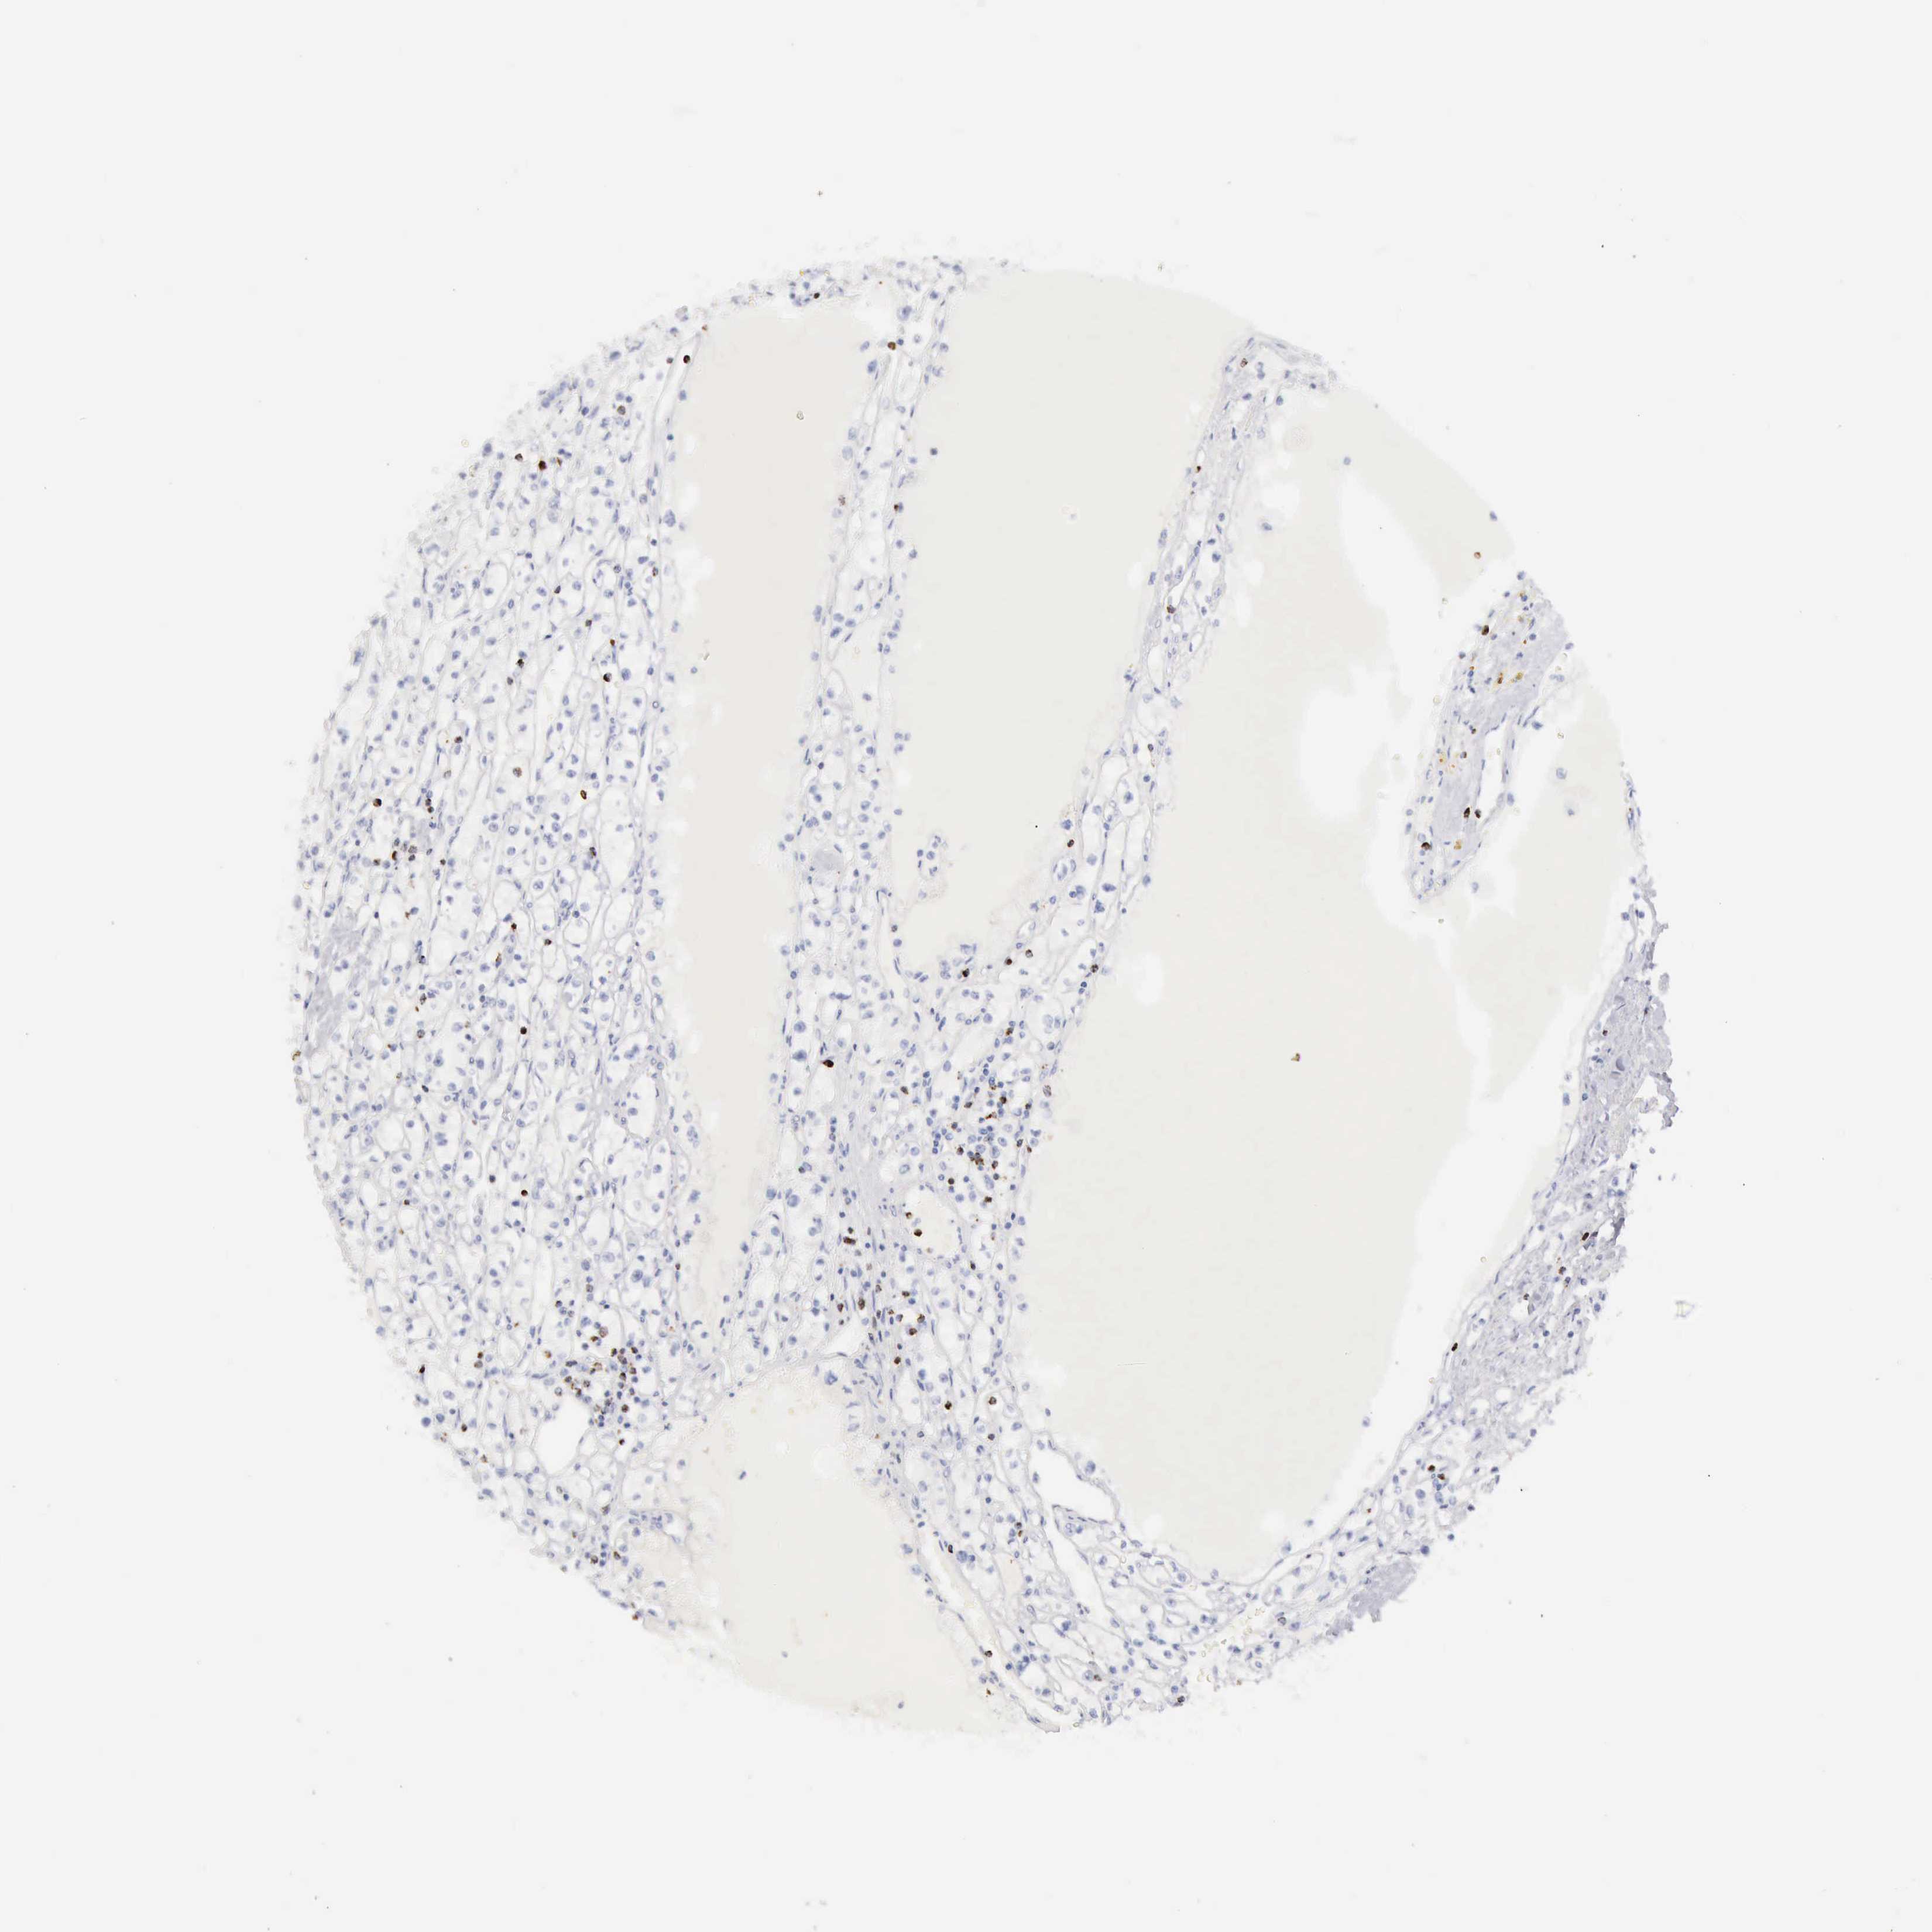

CANCER RENAL CANCER Show tissue menu

Renal cancer

Kidney chromophobe

KIDNEY CHROMOPHOBE (TCGA) - Interactive survival scatter ploti

The Survival Scatter plot shows the clinical status (i.e. dead or alive) for all individuals in the patient cohort, based on the same data that underlies the corresponding Kaplan-Meier plots. Patients that are alive at last time for follow-up are shown in blue and patients who have died during the study are shown in red.

The x-axis shows the expression levels (FPKM) of the investigated gene in the tumor tissue at the time of diagnosis. The y-axis shows the follow-up time after diagnosis (years). Both axes are complimented with kernel density curves demonstrating the data density over the axes. The top density plot shows the expression levels (FPKM) distribution among dead (red) and alive patients (blue). The right density plot shows the data density of the survived years of dead patients with high and low expression levels respectively, stratified using the cutoff indicated by the vertical dashed line through the Survival Scatter plot. This cutoff is automatically defined based on the FPKM cutoff that minimizes the p-score. The cutoff can be changed by dragging the vertical line or by entering a cutoff value in the square labeled "Current cut-off".

Under the Survival Scatter plot the p-score landscape (black curve; left axis) is shown together with dead median separation (red curve; right axis). Dead median separation is the difference in median mRNA expression between patients who have died with high and low expression, respectively. It is calculated as follows: median FPKM expression of dead patients with high expression - median FPKM expression of dead patients with low expression. This is intended to aid the user in visually exploring custom cutoffs and the associated p-scores and dead median separation.

Individual patient data is displayed and can be filtered by clicking on one or more of the category buttons on the top of the page. Categories describing expression level and patient information include: high, low, alive, dead, female, male and tumor stages. The scale of the x-axis can be toggled between linear and log-scale by clicking on the "x log" button. Mouse-over function shows TCGA ID, patient information and mRNA expression (FPKM) for each patient.

& Survival analysisi

Kaplan-Meier plots summarize results from analysis of correlation between mRNA expression level and patient survival. Patients were divided based on level of expression into one of the two groups "low" (under cut off) or "high" (over cut off). X-axis shows time for survival (years) and y-axis shows the probability of survival, where 1.0 corresponds to 100 percent.

GZMB is not prognostic in Kidney Chromophobe (TCGA)